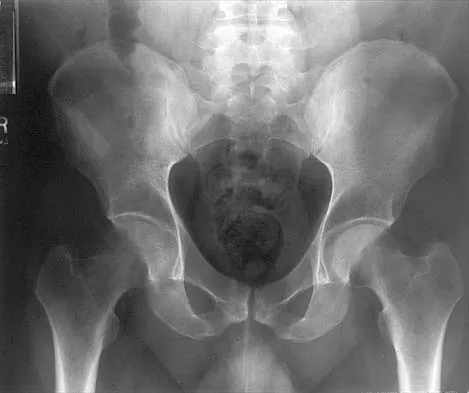

A 19-year-old woman reports lower back pain following a motor vehicle accident. Radiographs obtained immediately after the accident and a bone scan obtained 4 weeks later are shown in Figures 25a through 25c. The patient asks questions regarding the cause, genetics, and natural history of her condition. She should be informed that the condition was

Explanation

The radiographs show L5 spondylolysis without spondylolisthesis (slip). The bone scan is normal, indicating that the pars interarticularis fractures are not acute. The incidence of spondylolysis is approximately 5% in the general population. The lesion generally develops in children age 5 to 6 years, and there is a second peak in the adolescent population. There is a familial predisposition, with reported rates of 27% to 69% in close relatives. A recent long-term follow-up study found that 90% of the spondylolisthesis had occurred before the patient's first visit to the physician. Spondylolisthesis tends to progress during the initial growth spurt and is similar in some respects to idiopathic scoliosis. Progression of a lytic spondylolysis to spondylolisthesis in adulthood has been reported; however, this is exceedingly rare. Lauerman WC, Cain JE: Isthmic spondylolisthesis in the adult. J Am Acad Orthop Surg 1996;4:201-208. Hensinger RN: Spondylolysis and spondylolisthesis in children and adolescents. J Bone Joint Surg Am 1989;71:1098-1107. Seitsalo S, Osterman K, Hyvarinen H, Tallroth K, Schlenzka D, Poussa M: Progression of spondylolisthesis in children and adolescents: A long-term follow-up of 272 patients. Spine 1991;16:417-421.